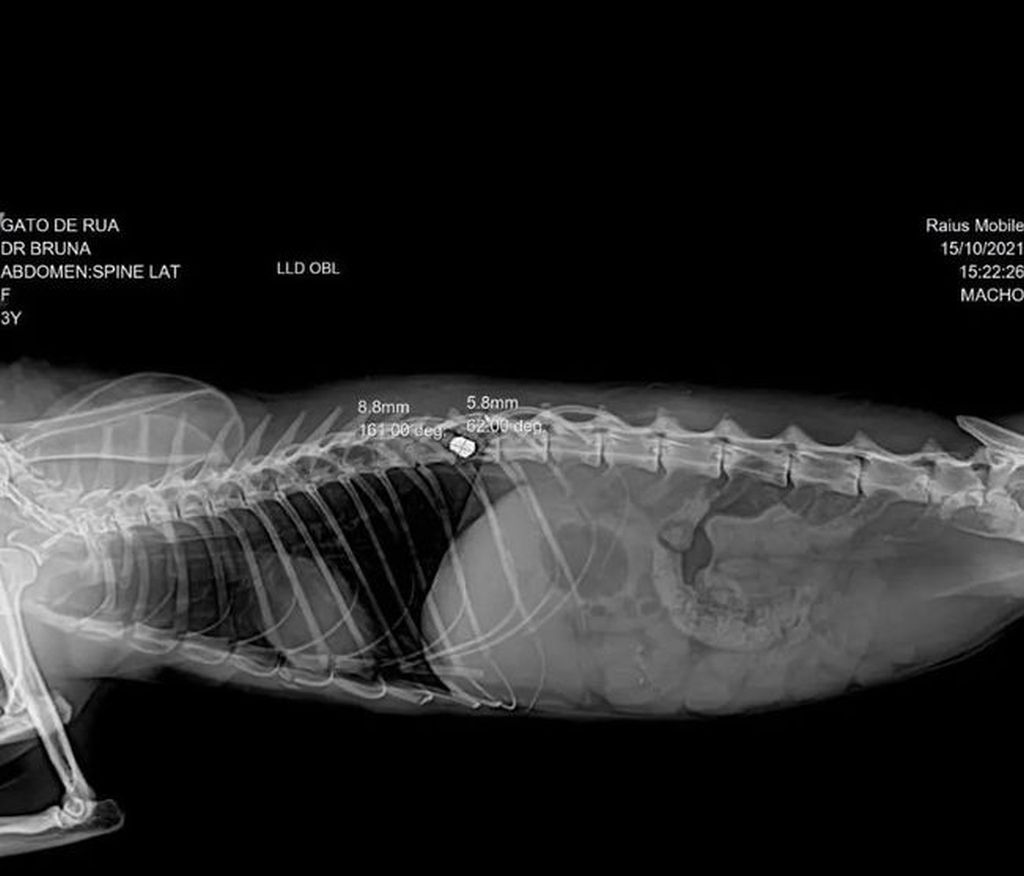

Após recolher o animal na quinta-feira, Ellen levou para uma clínica veterinária em Astorga. O gato ficou internado tomando soro e medicação para dor. O resultado do exame de raio-x saiu na sexta-feira, 15, indicando paraplegia por conta de uma bala que acertou a medula e está alojada na coluna. De acordo com ela, a cirurgia para retirada do projétil precisa ser feita o quanto antes para que o animal pare de sentir dor. Para realizar o procedimento, que deve custar R$ 2 mil, Ellen está pedindo doações.

Raio-x indicou a presença de uma bala de arma de fogo na coluna do gato